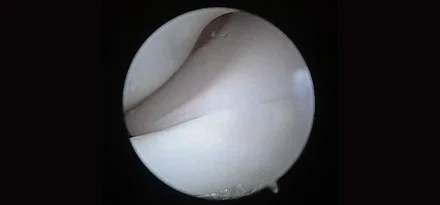

관절경

개,고양이 들은 다양한 관절질환이 존재하고, 복합적으로 존재하는 경우도 빈번합니다.

정확한 진단이 나지 않은 뒤 수술을 하게되면 증상개선이 더디거나 개선이 안될 수 있어, 정확한 진단이 필요합니다.

관절의 경우 X-ray 촬영등으로 진단의 한계가 명확하며, 상위 검사인 CT, MRI 촬영으로도 진단의 한계가 있습니다.

이때 관절경은 내부 구조물들을 직접 시각화 하여 보다 정확한 관절의 상태를 확인하고 진단할 수 있으며, 진단과 치료를 동시에 진행하는 경우도 있습니다. 대표적으로 십자인대단열(CCLR), 골연골염(OCD), 자뼈꿈치돌치유합부전(UAP), 내측관상돌기질환(MCD) 등에 활용될 수있습니다.

관절경 팔꿈치관절(Elbow) 확인

관절경 무릎관절(Stifle) 확인 (반월판 및 십자인대)

* 리본동물의료센터 케이스 사진으로 무단 복제 및 도용을 금지합니다.